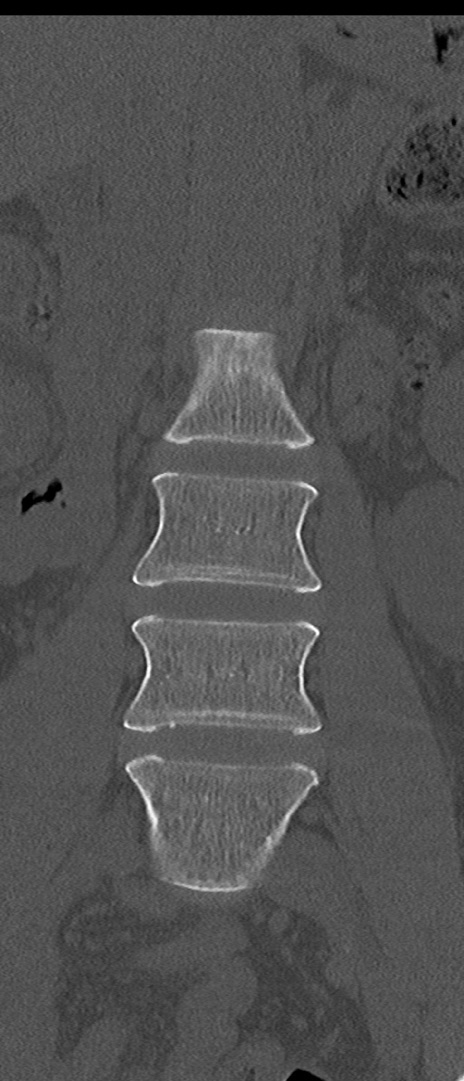

腰椎CT

矢状断像